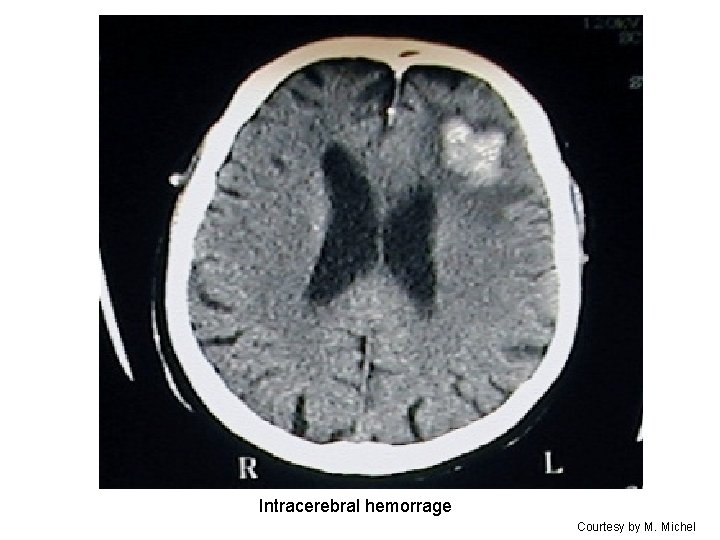

Intracerebral hemorrage Courtesy by M. Michel